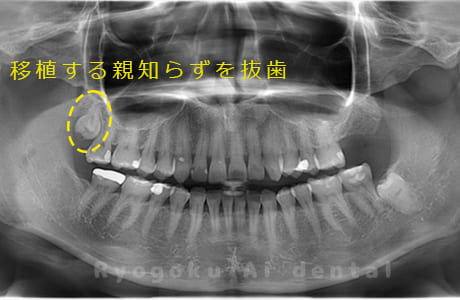

Case27

-

重度カリエス

歯牙移植咬合面術前 -

移植する親知らず

歯牙移植術直後咬合面

歯牙移植術後咬合面

歯牙移植術前側面

歯牙移植術中側面

歯牙移植術後側面

- 原因

- 重度カリエス

- 治療内容

- 自家歯牙移植、部分矯正

- 治療費用

- 220,000円(移植費用)

110,000円(部分矯正費用)

虫歯が大きく、保存不可能となった歯を上の親知らずと交換する自家歯牙移植を行いました。移植歯が小ぶりであったため、部分矯正を行い問題なく噛み合い、経過良好です。